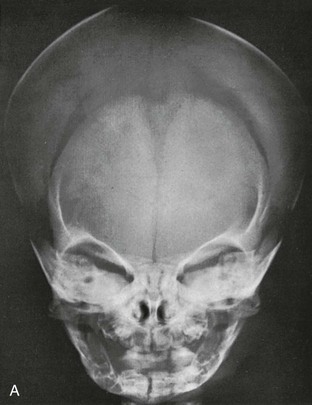

Анатомия детского черепа: Рентгеновские снимки и описание